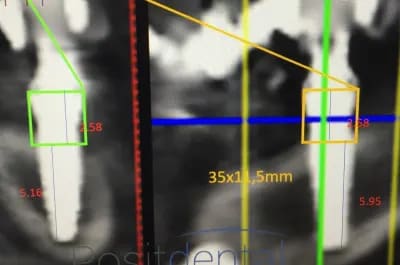

mais posit... y'a que toi qui pense que l'implant est aussi enfoui... ca saute aux yeux que tu fais tout pour grater 1mm d'enfouissement... pour qu'ils paraissent pas si mal posé que ca...

avec, par exemple, ton implant de 10mm qui est contenu dans 9mm... t'es le Gérard Majax des guides chir.

comme ici... si e carré fait 4,5 alors l’implant ne fait pas 10 mais moins de 9...

Tout comme l’autre implant pas 11,5 mais 10,3

heureusement que ta méthode est "précise" ;)

En traçant le col de l'implant comme tu le fais tu ne tiens pas compte que le pilier fait 4,5 mm de hauteur, normalement tu devrais arriver à le comprendre tout seul !